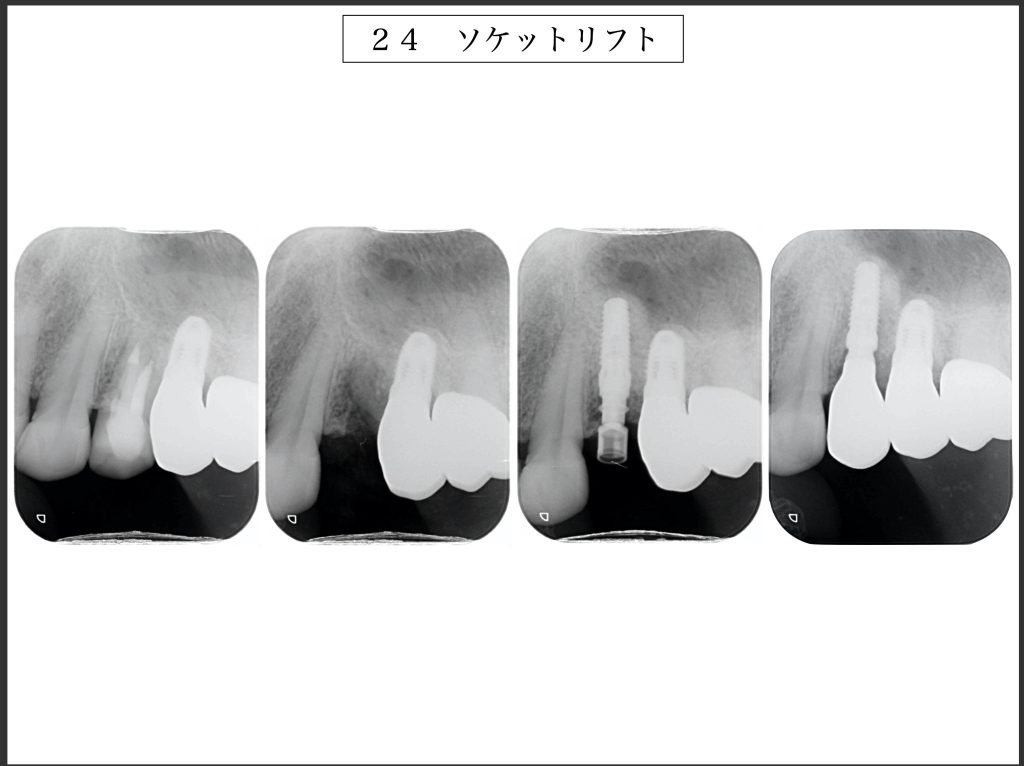

下記の症例は垂直的骨量が不足していた為、上顎洞粘膜を挙上し、同時にインプラントを埋入しました。

治療期間は4ヶ月ほどで最終補綴物を装着して終了しました。